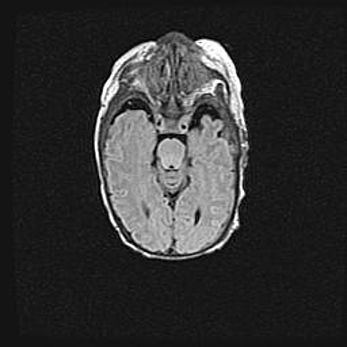

Множественные кисты обоих полушарий головного мозга, наибольшая из них в правой затылочной области. Ассиметричная атрофическая гидроцефалия.

Возраст: 7 месяцев

Вес: 5660 г

Пол: мужской

Окружность головы: 41,5 см

Срок гестации: 28-29 недель

Кисты головного мозга развиваются в результате многоочаговых некрозов вещества мозга и возникают вследствие перенесенной перинатальной инфекции, менингитов, энцефалитов, асфиксии, родовой травмы, расстройств мозгового кровообращения различного генеза. Образованию кист в веществе головного мозга плодов и новорожденных способствуют такие факторы, как высокое содержание в нем воды, недостаточная (или отсутствие) миелинизация и слабая астроглиальная реакция на повреждение.

Кисты могут сочетаться с гидроцефалией и другими поражениями головного мозга.